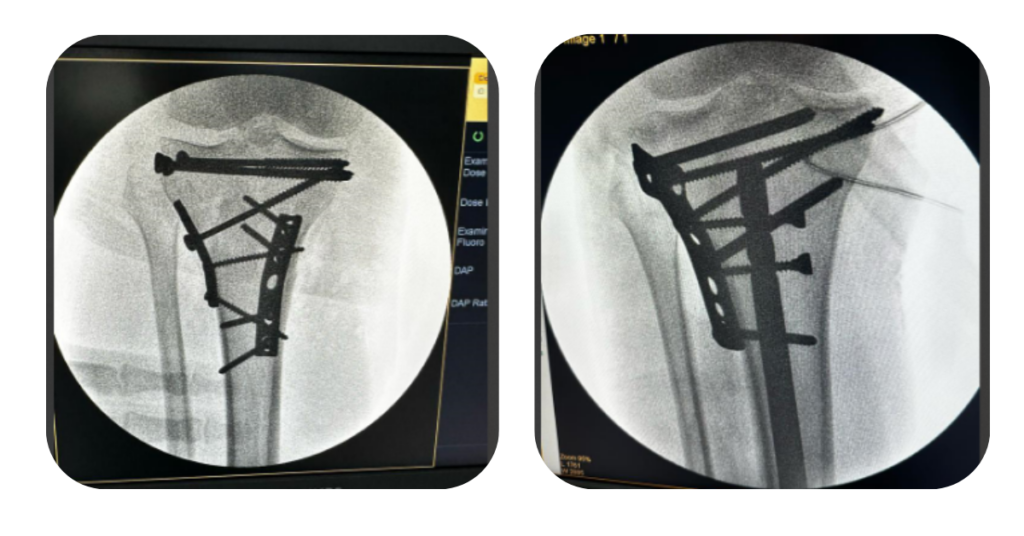

A cirurgia geralmente envolve a fixação com placas, parafusos ou fios metálicos, e em casos mais graves, pode ser necessário o uso de prótese parcial.